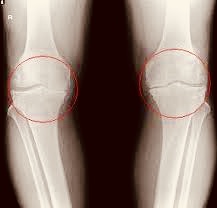

お膝はこんな形をしています。

上側の骨が、太ももの骨。

下側の骨が、すねの骨です。

膝の関節、といえば

この2つが代表的な骨になります。

さて、レントゲン上には

これらの骨しか写っていませんが、

実際は違いますよね?